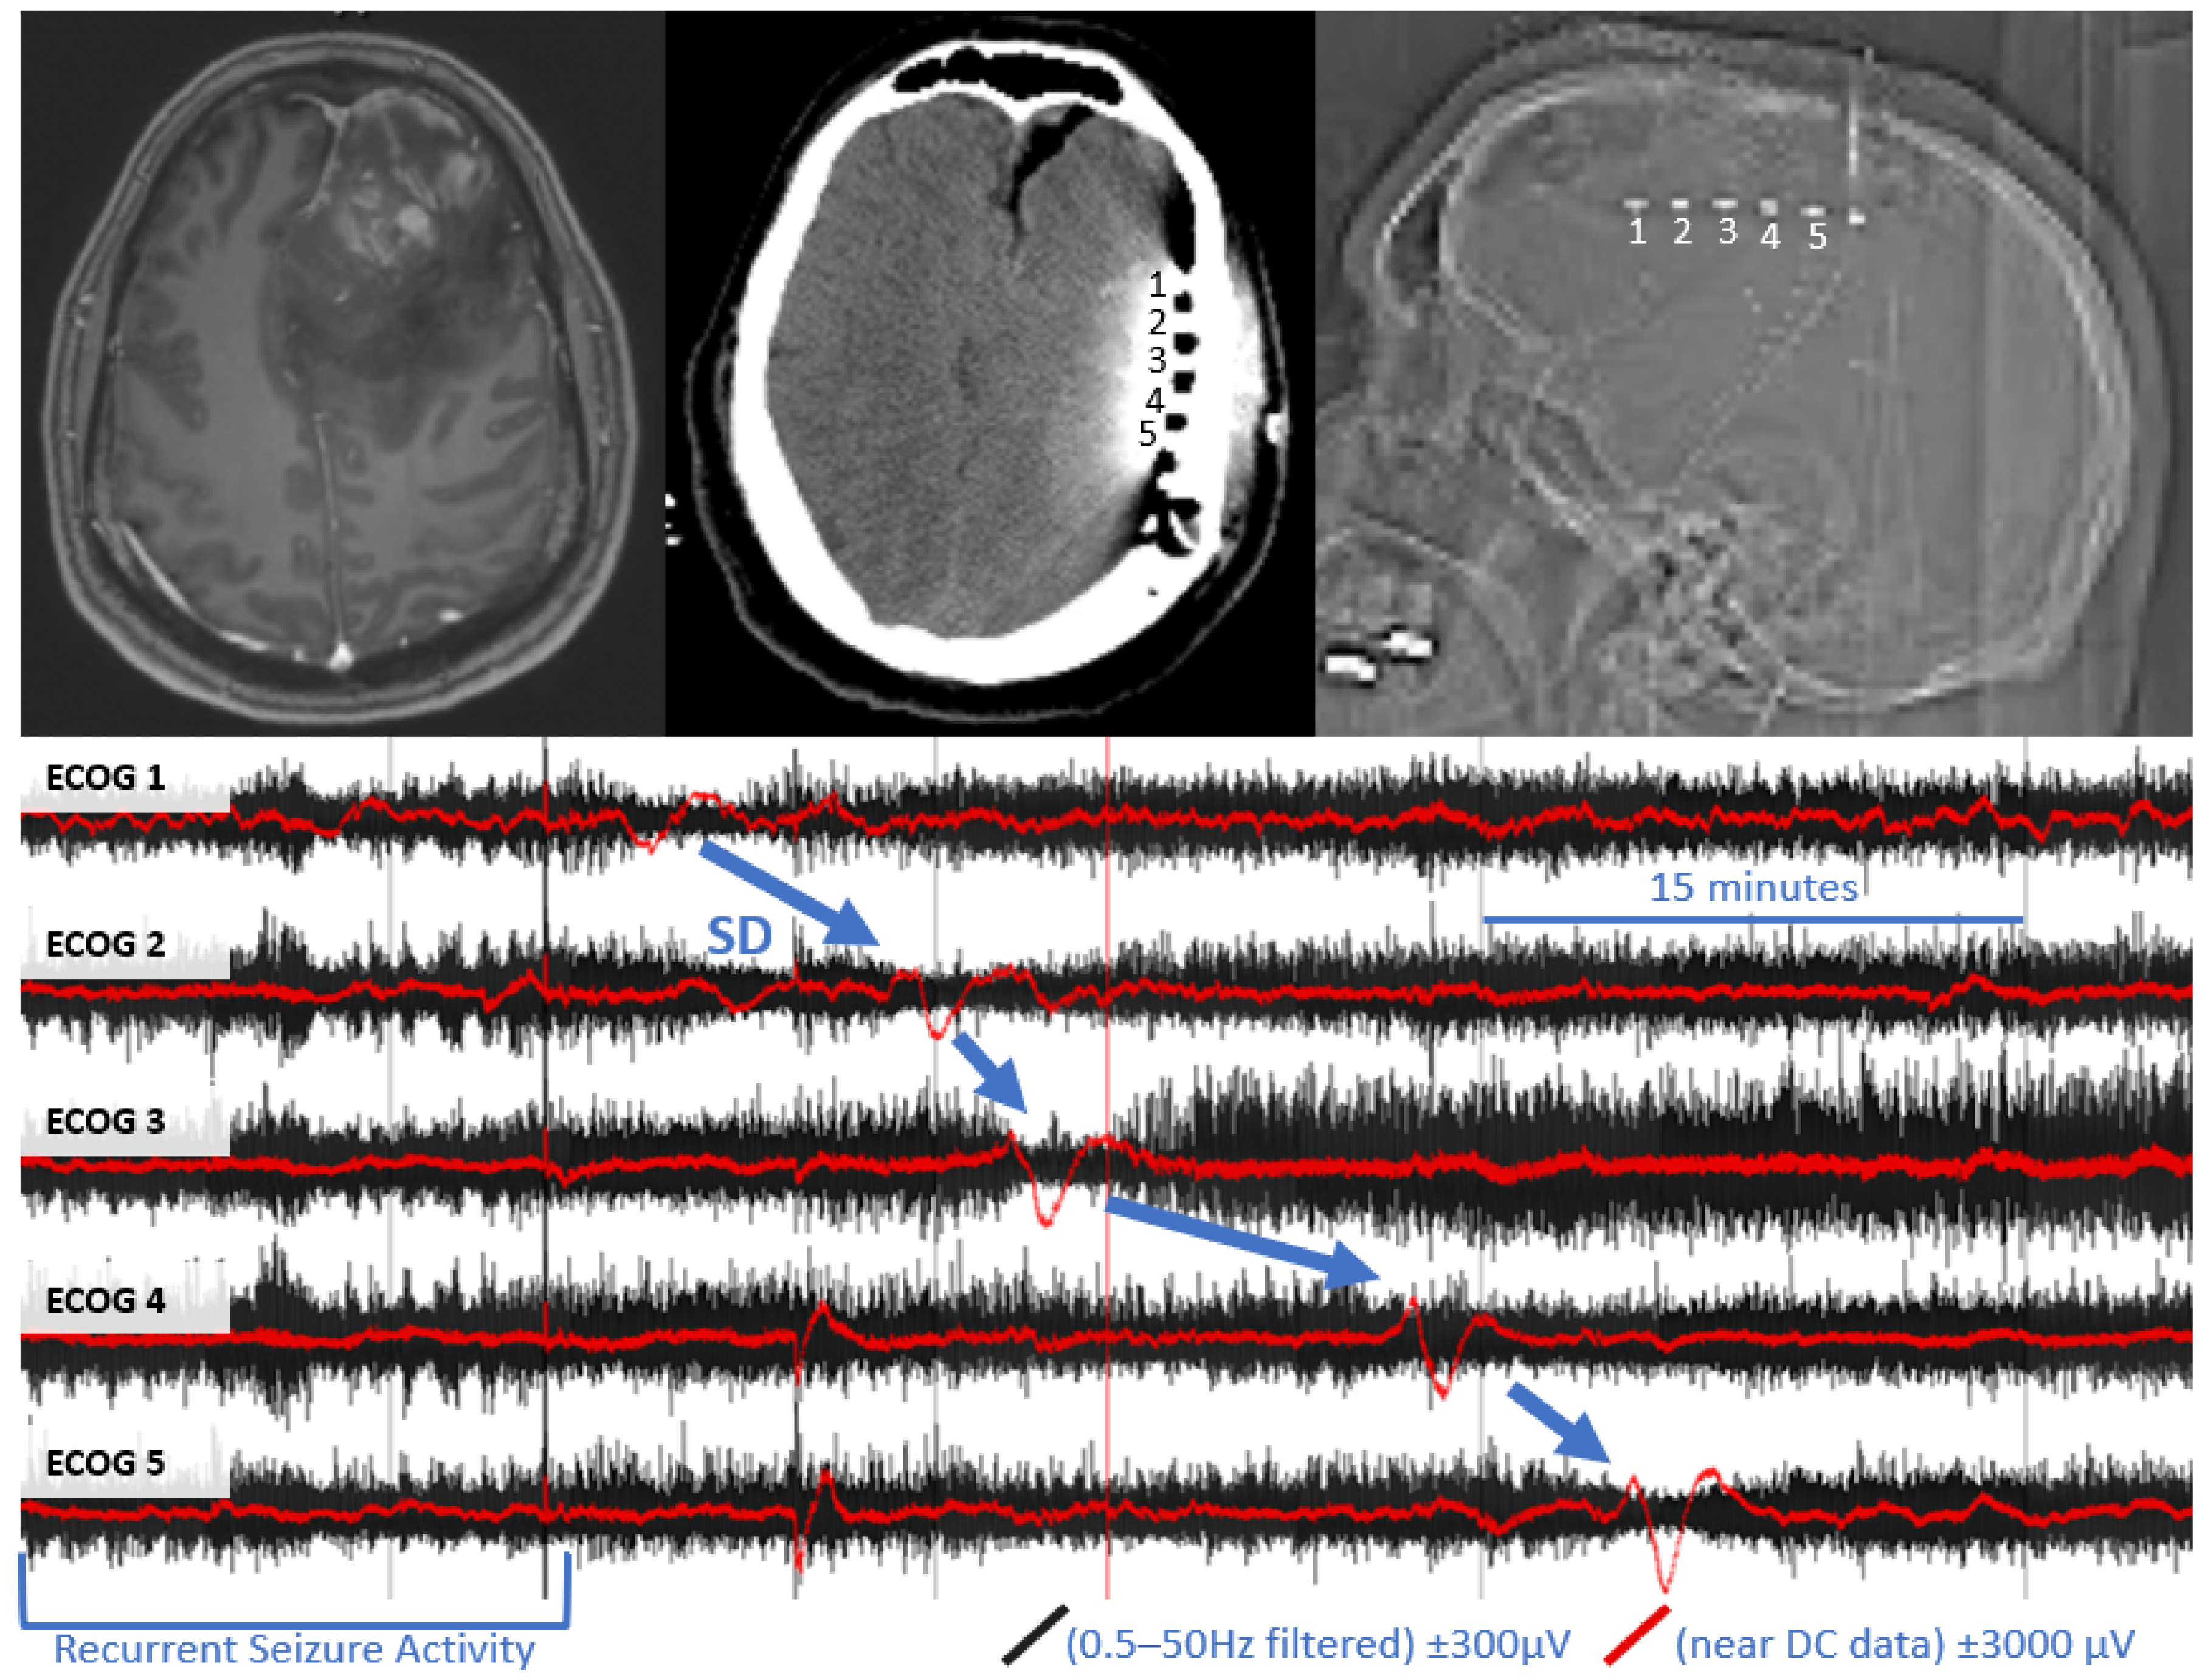

In one subject, we were able to clearly detect four definite SD with characteristic DC shift and transient suppression of high frequency activity (see Figure 1). These events appeared to originate from the anterior electrodes, closest to the tumor cavity. A total of 59 h, 52 min of recording time was available in this subject, which was notably more than the other two subjects in whom SD was not detected (23 h, 4 m and 26 h, 6 m). In the subject with SD, there were several electrographic seizures throughout monitoring, including several cyclic seizures that occurred prior to the onset of the most significant SD.

Figure 1. Example of spreading depolarization in a patient with high grade glioma. Upper left panel: pre-operative MRI with and without contrast, demonstrating contrast enhancing left frontal mass with surrounding vasogenic edema. Upper middle panel: post-operative CT, demonstrating the location of the subdural electrode (labeled 1–5) posterior to the tumor resection bed. Upper right panel: scout film from CT also demonstrating the location of the electrode. Bottom panel: referential traces from contacts 1–5 (1 is closest to tumor bed). The black traces represent time compressed, high frequency ECoG data, filtered a 0.5–50 Hz. Overlying red traces represent the same data near DC traces (>0.005 Hz for baseline leveling). A propagating wave of DC shift/slow potential change (in red) that is accompanied by transient suppression of high frequency signaling (in black) is demonstrated (blue arrows).